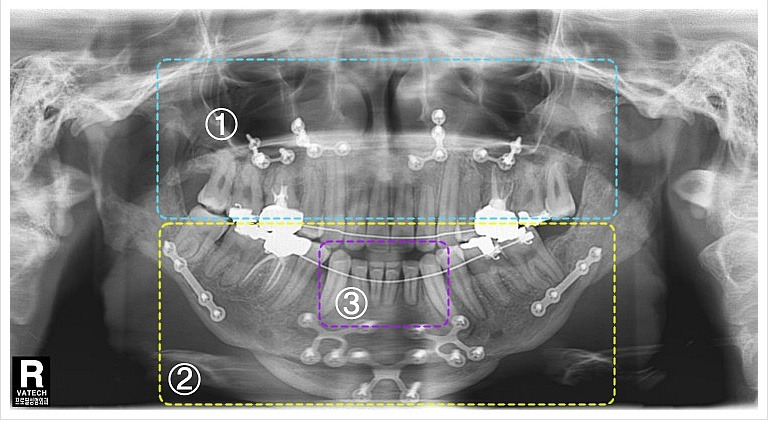

삼악수술은 턱의 세 가지 주요 부위를 동시에 교정하는 수술입니다. 일반적으로 돌출입과 하악왜소증을 동시에 개선하기 위해 시행됩니다. 이 수술은 턱의 위치를 조정하고, 교합을 개선하여 기능적인 문제를 해결하는 데 중점을 둡니다.

삼악수술의 전후 비교

수술 전에는 턱의 비대칭이나 돌출입으로 인해 고민했던 많은 사람들이 수술 후에는 이러한 문제들이 해소되어 자신감이 높아지는 모습을 보입니다.

수술 전후의 사진을 비교해 보면 얼굴의 형태가 얼마나 달라졌는지를 쉽게 확인할 수 있습니다.